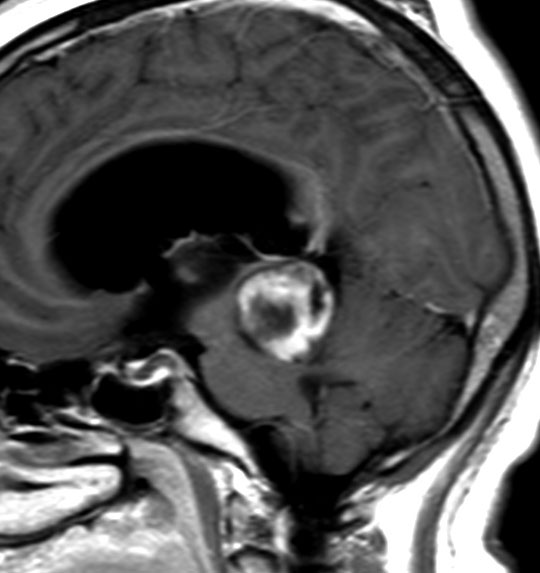

毛様細胞性星細胞腫であり,基本的には初回手術で全摘出できるのですが,現実的には,技術的に難しすぎるので部分摘出で終えることが多いでしょう。この子は,15歳の時に閉塞性水頭症のために,頭痛,嘔吐,意識障害,瞳孔不同となりました。開頭部分摘出術と第3脳室開窓術で回復して,その後にカルボプラチンとビンクリスチンの化学療法を受けました。

でも腫瘍増大が止められずに,発症1年後に54グレイ30分割の放射線治療を受けています。さらにその半年後くらいから再増大しましたが,スードプログレッションと考えられました。上左MRIは放射線治療前,上右MRIは放射線治療1年後です。毛様細胞性星細胞腫は放射線治療後に一過性増大(多くはのう胞性増大)することが多いです。

のう胞性拡大が止まらず,発症3年後にまた再開頭手術 (left occipital transtentorial approach) で亜全摘出しました。右は術後の画像です。初発時の最初の手術で亜全摘出あるいは全摘出 gross total removalできていればと思える例です。